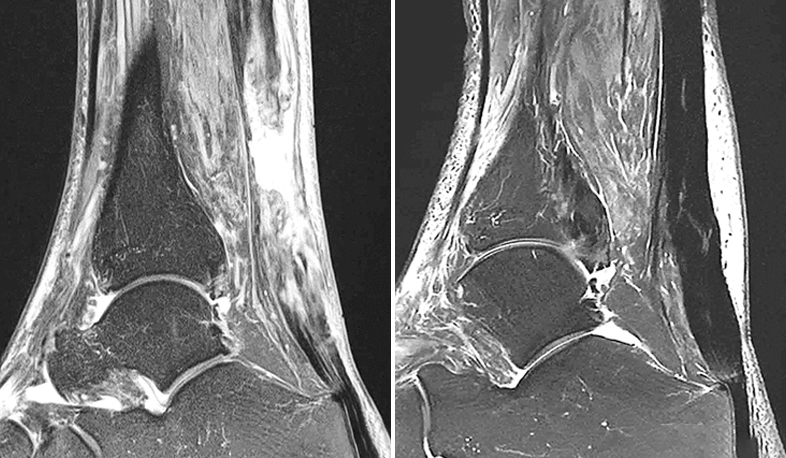

El tratamiento incluye no solo la aplicación del medicamento, sino un seguimiento clínico individualizado que puede extenderse entre 2 y 5 años, dependiendo de la patología. Durante este periodo se realizan controles funcionales y estructurales periódicos, que incluyen pruebas de imagen como resonancia magnética, con el objetivo de evaluar la evolución clínica del paciente, la estabilidad del efecto biológico y la seguridad a largo plazo.